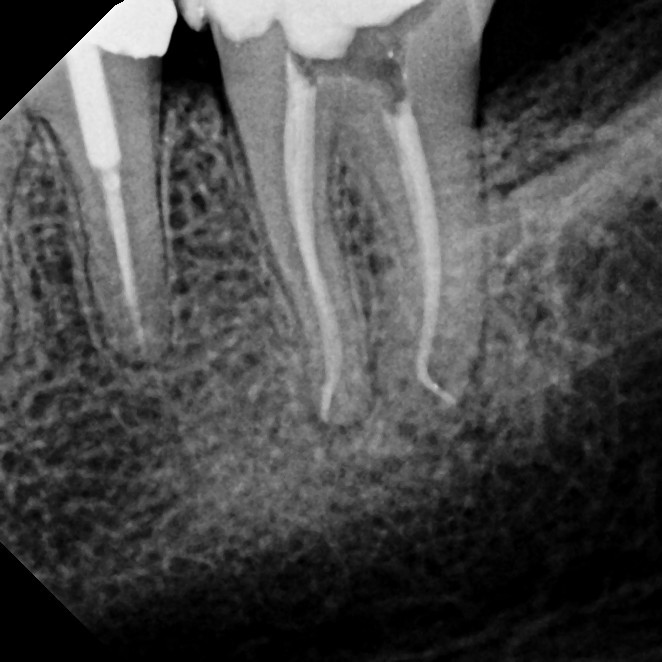

Root Canal Therapy

Root canal therapy is a specialized treatment designed to save a tooth that has been damaged by deep decay, trauma, or infection. Sometimes the problem causes noticeable pain or sensitivity, but in other cases it may develop quietly without obvious symptoms. During the procedure, the infected or damaged nerve tissue inside the tooth is carefully removed, the canals are disinfected, and the space is sealed to prevent further problems. Local anesthesia ensures you're completely comfortable throughout the process.

Thanks to advances in modern dentistry, root canals have become far more comfortable and efficient than they were in the past. Most patients report that the experience is comparable to having a standard filling, and recovery is typically quick. By treating the tooth promptly, you can avoid more serious dental issues, preserve your natural smile, and return to normal function without the need for extraction.